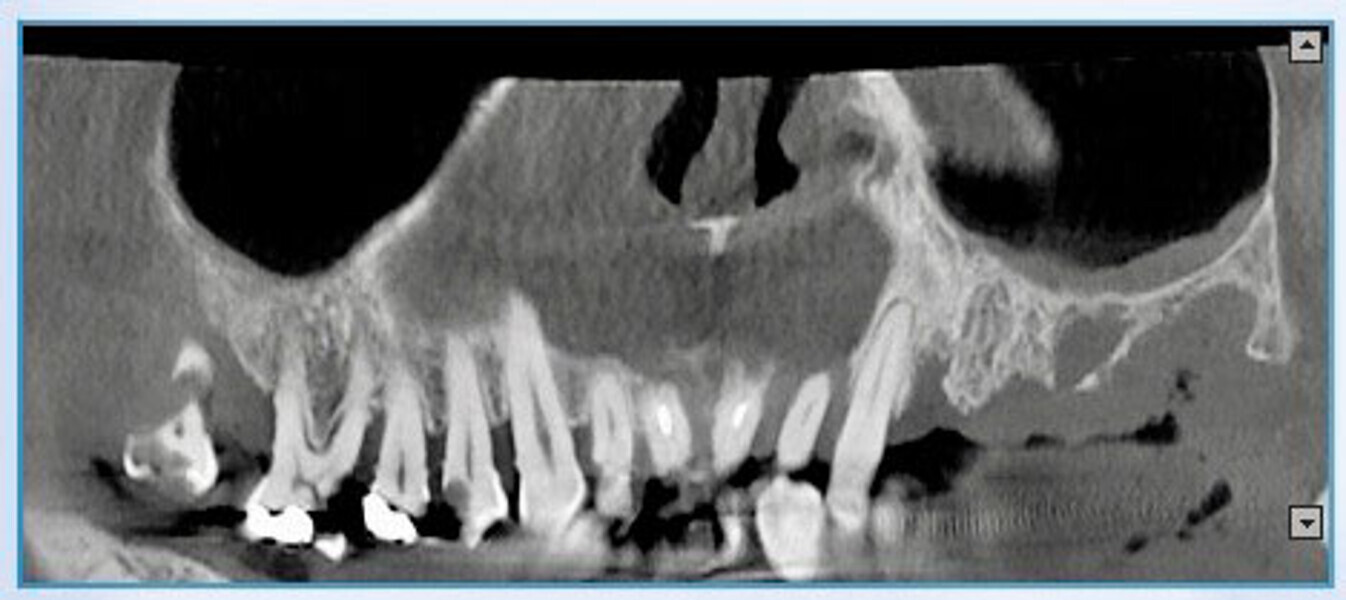

Protocollo SKY fast & fixed